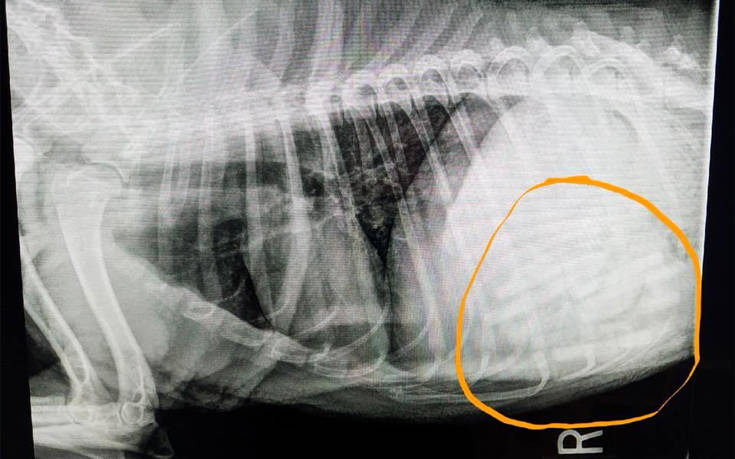

Μια πιπίλα βρισκόταν στον πάγκο της κουζίνας και με μια κίνηση ο σκύλος την έπιασε και την κατάπιε. Η επίσκεψη στον κτηνίατρο και συγκεκριμένα όσα βρέθηκαν στο στομάχι του σκύλου θα έδιναν την απάντηση. Μέσα σε αυτό βρέθηκαν όχι μία, όχι δύο, αλλά 21 πιπίλες του μωρού.

Αρχικά, ο κτηνίατρος περίμενε να βρει επτά με οχτώ πιπίλες στο στομάχι της Dovey, η εγχείρηση όμως έδειξε άλλα.